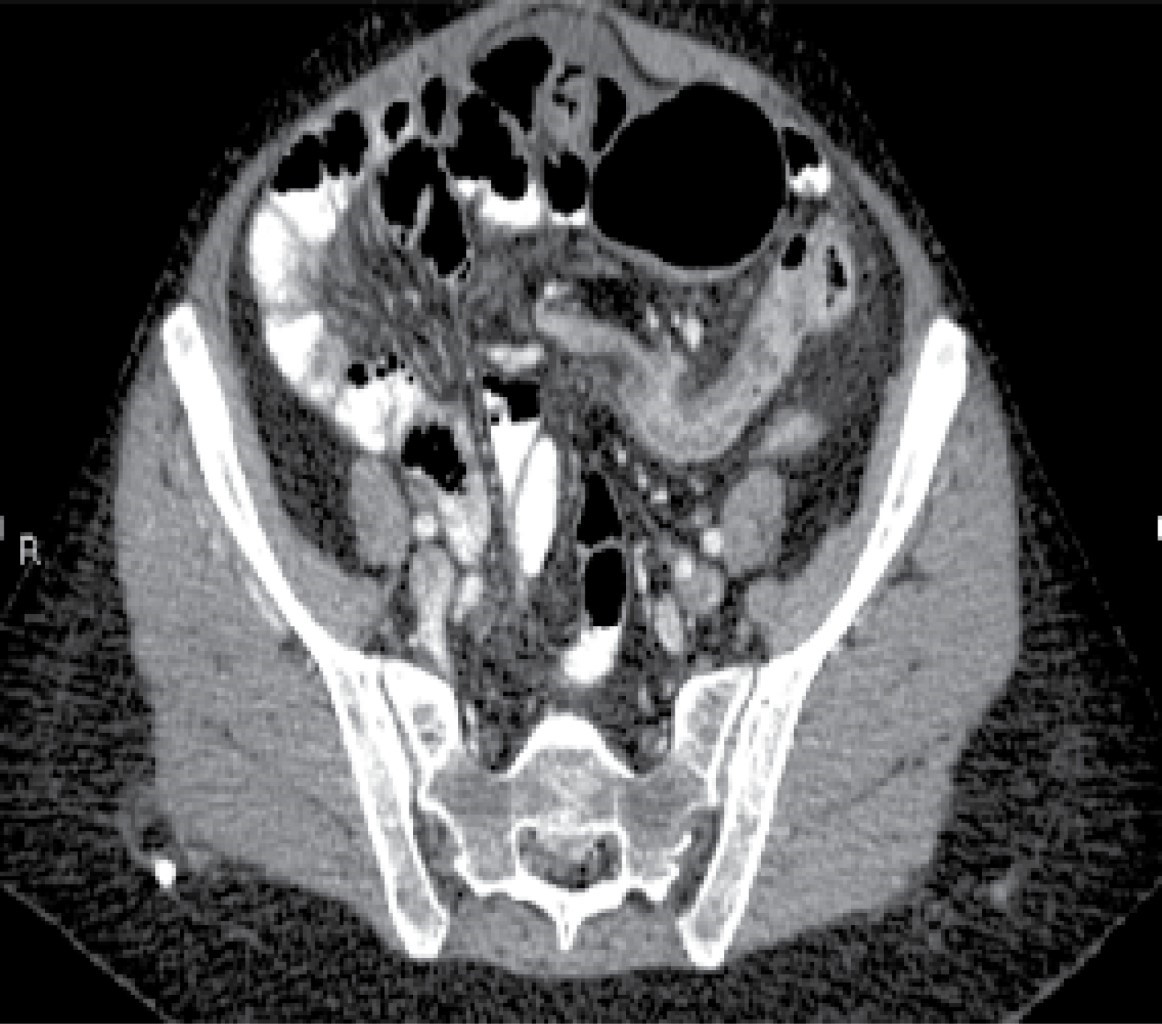

Laboratory studies were requested, which reported 12,000 leukocytes per cubic millimeter, seven-band forms, and serum lactate levels of 2.8 mmol/l. Subsequently, an abdominal tomography with double contrast was performed, finding significant cecal dilatation, the ascending colon and the proximal portion of the transverse colon, and a transition zone towards the distal third located in the left iliac fossa. Likewise, a supraumbilical abdominal wall hernia is found in the midline with scarce fatty tissue and omentum (Figures 1, 2, 3 and 4).

Figure 2